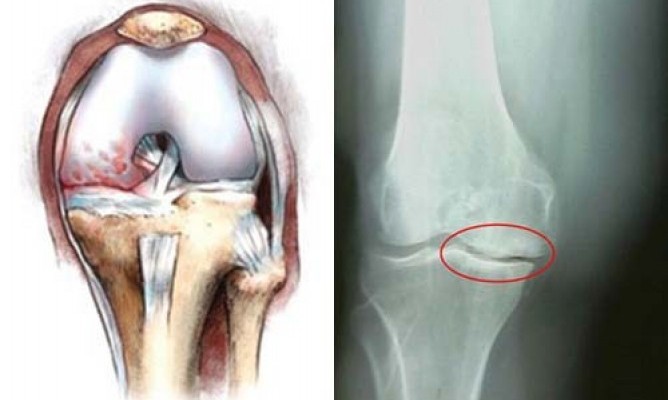

Артроз – это поражение гиалинового хряща сустава. Этот хрящ постепенно разрушается. Сначала изменяется его структура, плотность, потом он становится всё тоньше. В тяжелых случаях хрящевая ткань может полностью отсутствовать.

- При осмотре врач отмечает небольшие изменения в форме сустава. Если сделать рентген, будет видно, что суставная щель слишком узкая, а на костных краях формируются разрастания.

- На рентгеновском снимке видно отсутствие хряща на многих участках суставной поверхности, склероз кости. Суставная щель резко сужена, обнаруживается большое количество остеофитов.